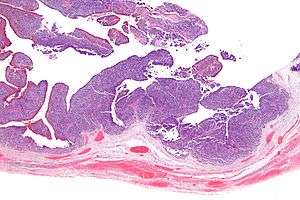

Low mag.

TCC of the ovary is diagnosed by examination of the tissue by a pathologist. It has a characteristic appearance under the microscope and distinctive pattern of immunostaining.[2]

It is not related urothelial carcinoma.[1] It is in the transitional cell category of ovarian tumours which also includes malignant Brenner tumour and benign Brenner tumour.